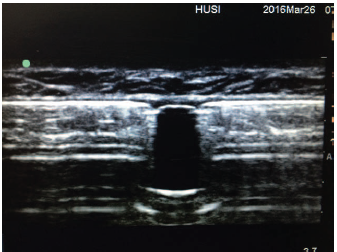

Utilizando Ecógrafo Sonosite EDGE con transductor lineal de alta frecuencia y parámetros para tejidos blandos, profundidad 2.7 cm, definición en resolución, se ubica el transductor sobre pared abdominal en área de la bomba para identificar su cara anterior y contornos. Se ubica el cuerpo de la bomba, visualizando una línea hiperecóica con sombra aaistica.

Se localiza el puerto de ingreso, que se observa como una zona anecóica interrumpiendo la línea hiperecóica descrita (Figura 2). Se ubica el puerto en el centro de la pantalla, correspondiendo al centro del transductor.